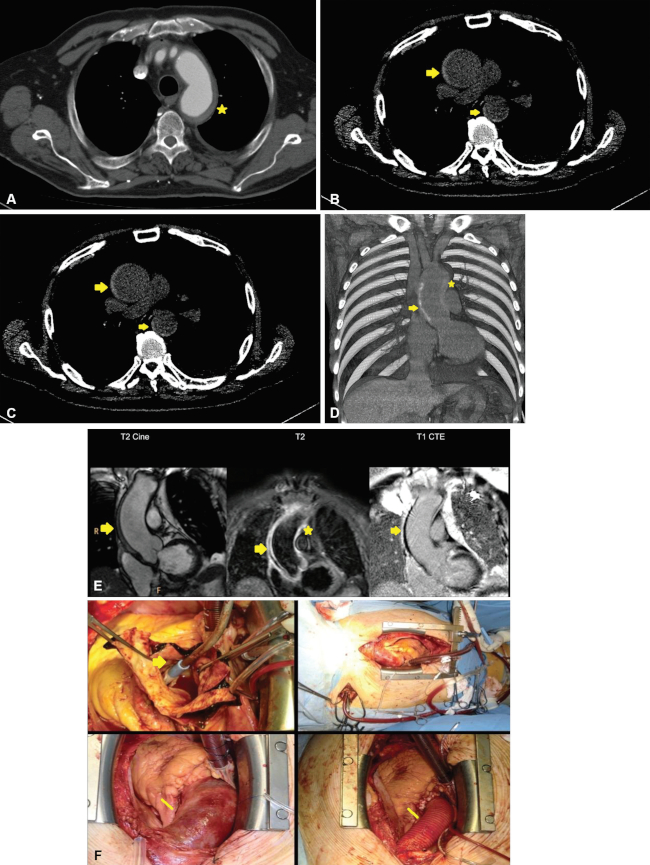

Espondilitis anquilosante

Afecta a la raíz de la aorta y a la válvula aórtica en el 80% de los casos.

Mediante TCMD, se evidencia engrosamiento de la pared aórtica, presente en aproximadamente el 60% de los pacientes afectados, y de la válvula aórtica con modularidad y consecuente insuficiencia.1

La inflamación celular de la raíz aórtica resulta en una marcada respuesta fibroblástica reparadora, engrosamiento de la capa adventicia, destrucción focal del tejido elástico y proliferación de la íntima. La inflamación circundante produce endarteritis obliterante y luego dilatación de la raíz. Esos cambios crónicos o agudos de la raíz aórtica y la válvula conducen a la insuficiencia aórtica.15

Aortitis idiopática

Es asintomática, diagnosticada por anatomía patológica; se presenta mayormente en mujeres como dilatación aórtica sin evidencia de síntomas de enfermedad sistémica. Puede evidenciarse engrosamiento irregular de la pared involucrando el arco aórtico y aorta ascendente.2

Aneurisma aórtico inflamatorio idiopático

Se distingue del aneurisma ateroesclerótico por presentarse con engrosamiento de la pared, acompañado por fibrosis densa que puede llegar a envolver estructuras adyacentes, tales como el duodeno, el uréter y la vena cava inferior. Ocurren en la porción infrarrenal de la aorta abdominal y en pacientes más jóvenes que los afectados por la causa aterosclerótica.2,16

Una característica distintiva del aneurisma inflamatorio idiopático es que el engrosamiento parietal afecta predominantemente la pared anterior del vaso (►Fig. 4.).1

El principal diagnóstico diferencial es la fibrosis retroperitoneal, en la que, además de reacción inflamatoria fibrótica, se observa dilatación de la aorta, y el aneurisma micótico, debido a la similitud clínica, imagenológica y laboratorio (elevación de la proteína C reactiva).2 En cuanto a las características imagenológicas, el aneurisma micótico suele ser sacular, irregular y pueden encontrarse burbujas aéreas circundantes, a diferencia del aneurisma inflamatorio que suele ser fusiforme (►Fig. 5).16